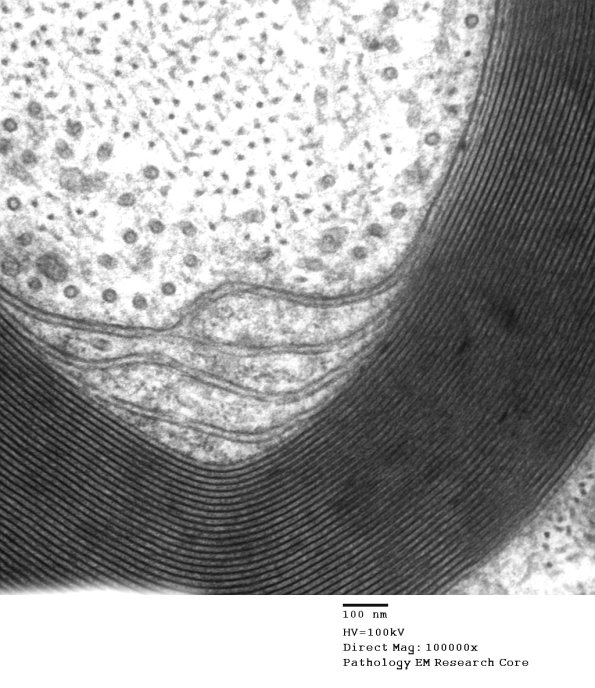

Washington University Experience | PERIPHERAL NEUROPATHY | 2 NORMAL AXON | 11A4 (Case 11) EM 004 - Copy

Higher magnification of image #11A1. (electron micrograph)